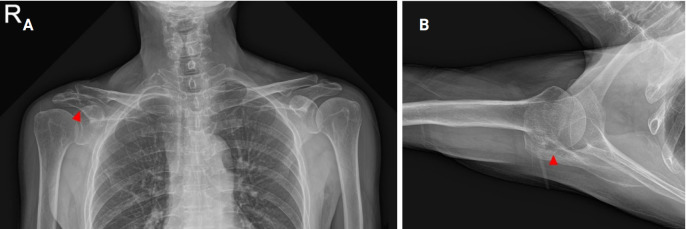

Epithelioid hemangioma of bone is a rare benign vascular tumor. Because of the locally destructive clinical presentation and the presence of atypical histologic features with increased mitotic activity and necrosis, it is often misdiagnosed as low-grade malignant epithelioid hemangioendothelioma or high-grade malignant epithelioid angiosarcoma. Correct diagnosis through imaging studies and histopathological examination is mandatory to determine the appropriate course of treatment, as the prognosis differs from that of other malignant hemangioma tumors. A 69-year-old male who presented with intractable shoulder pain caused by epithelioid hemangioma in the acromion of the scapula was treated with tumor curettage. This paper reports a good result with a review of the relevant literature.